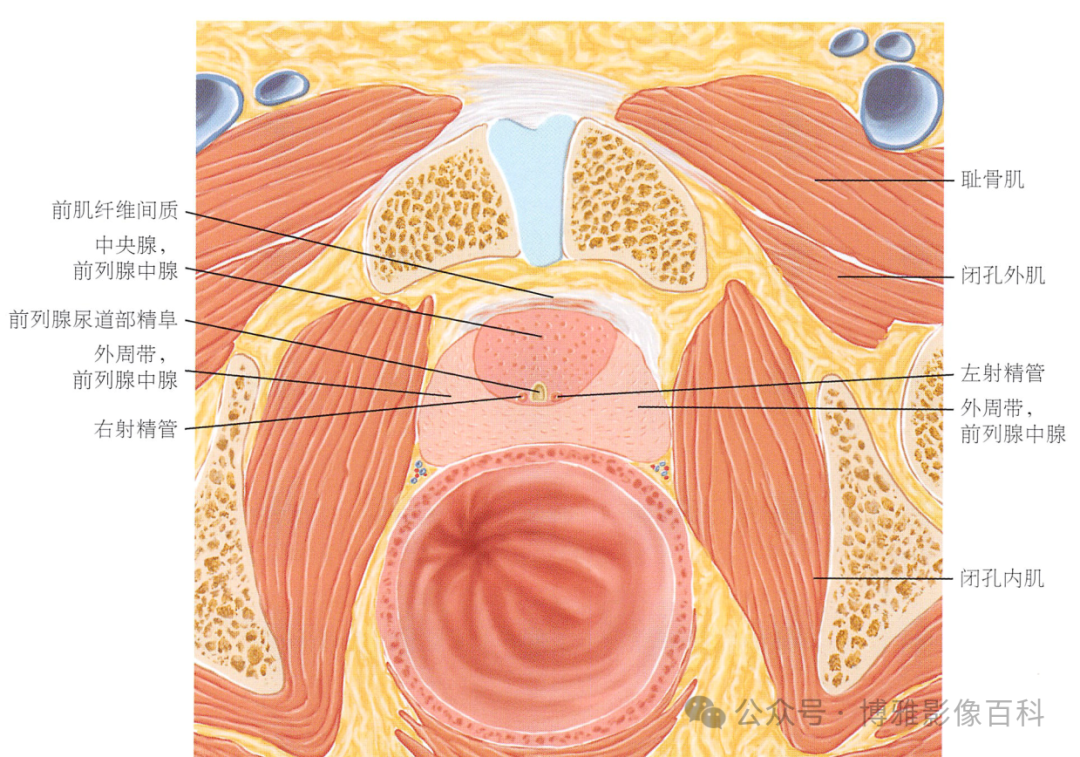

解剖学

前列腺分区解剖学

MR 解剖学